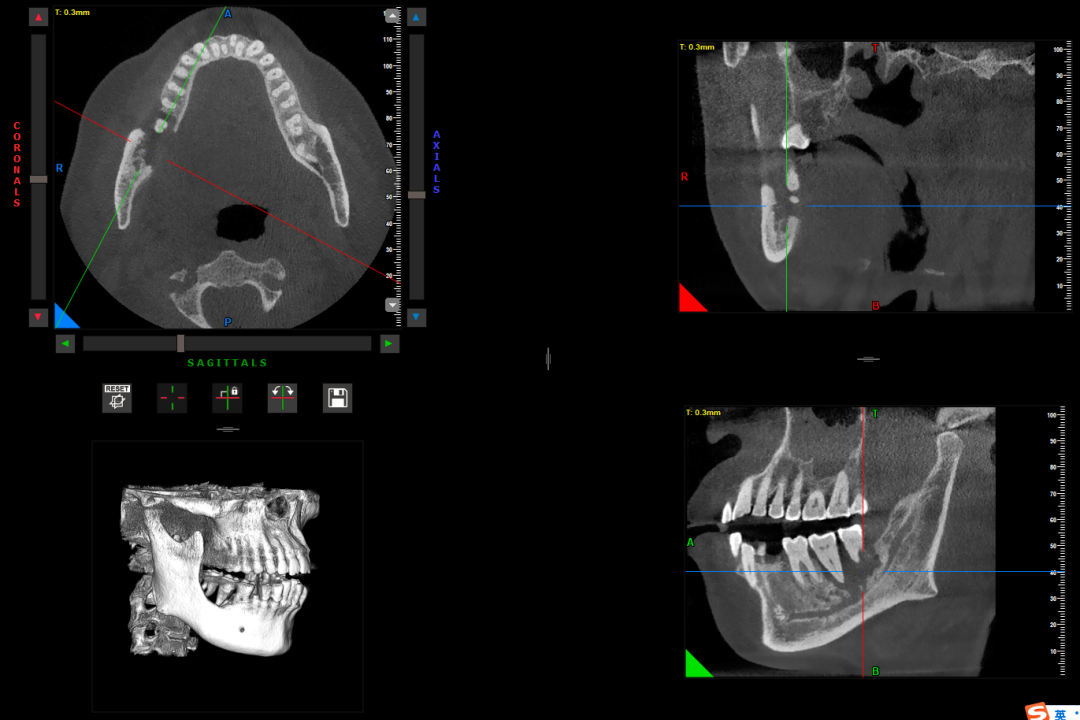

锥形束CT(CBCT)

锥形束CT是指放射线束呈锥形发出,围绕患者头部旋转获得扫描视野内的原始图像,从而进行三维观察及三维重建的数字容积体层摄影。

它可以从三维角度观察到每一颗牙齿、上下颌骨、血管神经、颞下颌关节的情况;可以清晰的观察到牙根折裂情况,囊肿的大小、位置及与牙齿牙根、神经的关系;可以显示多生牙、埋伏牙的位置关系;也能为口腔种植技术提供精准的颌骨测量指标。

CBCT可以从三维角度了解下颌骨病变